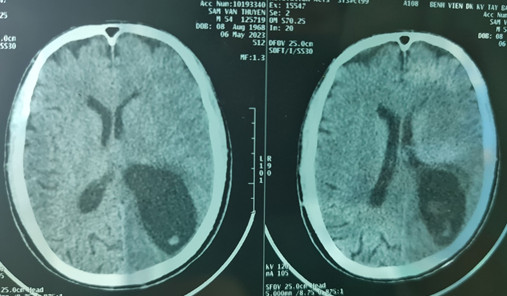

Hình ảnh phim chụp CLVT sọ não bệnh nhân S.V.Th trước khi phẫu thuật

Sau thăm khám, bệnh nhân đã làm các xét nghiệm cần thiết cho kết quả, xét nghiệm phân tìm ký sinh trùng (+), xét nghiệm ELISA chẩn đoán ấu trùng sán lợn Cysticercosis(+), chụp cắt lớp vi tính não cho thấy có nhiều ổ giảm tỷ trọng kèm phù não lớn vùng bán cầu trái.

Dựa vào những kinh nghiệm về chuyên ngành và những dữ liệu có được của y học về các triệu chứng lâm sàng, yếu tố dịch tễ, cận lâm sàng, công thức máu, kết quả chụp CT Scan. Sau hội chẩn, các bác sĩ chẩn đoán bệnh nhân bị Hội chứng tăng áp lực nội sọ do ấu trùng sán dây lợn trên hệ thần kinh, nguy cơ tử vong cao nếu không xử lý kịp thời.